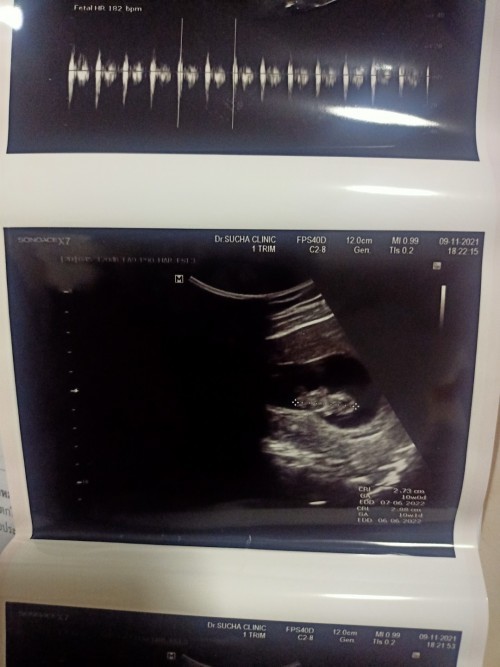

10wkค่ะ

10 วีค 2 วัน ค่ะ 3.83 cm